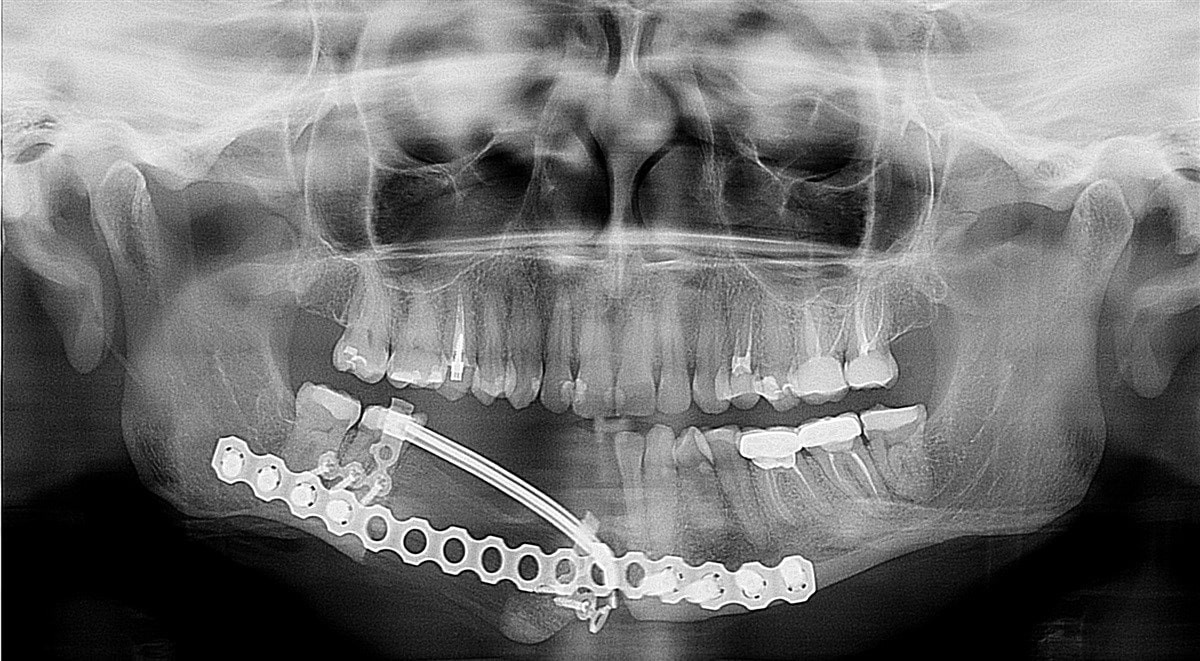

Примеры ортопантомограмм и их анатомия

Раздел: Фотоэссе